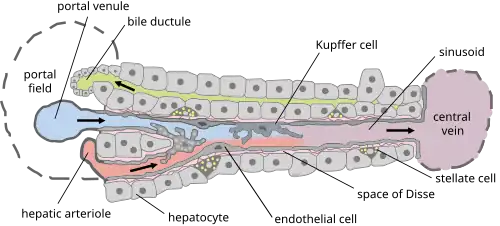

Fibrose péri-cellulaire

La production de tissu fibreux par diverses populations de cellules dont les plus importantes (mais non les seules) semblent être les cellules stellaires présentes dans l’espace de Disse. Ces cellules, responsables dans le foie sain, du stockage de la vitamine A et de graisses, sont activées en réponse à des lésions cellulaires et réagissent de façon à limiter ces lésions. Elles acquièrent pour ce faire des propriétés sécrétoires et contractiles, favorisant la prolifération des cellules fibrogéniques, leur contractilité et la production de tissu fibreux ; d’autre part, elles s’opposent à la dégradation du tissu fibreux nouvellement formé par la production d’inhibiteurs des métalloprotéinases[3]. Il a été démontré dans un modèle animal que ce phénomène est auto-régulé car les cellules stellaires activées entrent dans un processus de vieillissement cellulaire, produisent moins de tissu fibreux et sont plus facilement reconnues par les cellules tueuses naturelles[4].

Par ailleurs, elles obstruent le flux sanguin (chez l’individu sain, le sang provenant du tube digestif est emmené au foie par la veine porte jusqu'aux cellules hépatiques ; le sang revient dans la circulation générale par les veines sus-hépatiques qui se déversent dans la veine cave inférieure). Comme le sang ne peut plus circuler, il stagne dans le système porte, ce qui entraîne une augmentation de la pression dans ce dernier[5].

Formation de travées fibreuses

La perte localisée du parenchyme hépatique, à la suite de l’obstruction en cet endroit de la circulation se jetant dans la veine hépatique et dans la veine-porte. Si l’occlusion de l’un des deux vaisseaux ne provoque qu’une atrophie, une double obstruction entraîne une diminution de l’apport sanguin et aboutit à la formation de cloisons fibreuses se développant sur le trajet des vaisseaux obstrués. Ces cloisons comprennent, outre le tissu fibreux, des débris cellulaires, de petites fistules artérioveineuses et des vaisseaux sanguins nouvellement formés. Il s’agit donc d’un tissu cicatriciel se développant le long de vaisseaux sanguins ayant cessé d’alimenter la portion de tissu hépatique qu’ils desservaient.

La fibrose empêchant la reconstitution de lobules hépatiques normaux, la régénération des hépatocytes s’effectue de manière anarchique et aboutit à la constitution de « nodules de régénération » ayant perdu les connexions vasculaires et biliaires, avec stagnation de la bile dans les canaux biliaires intrahépatiques. Par ailleurs, l’hypertension portale résultant de la fibrose induit la formation de dérivations que constitue la circulation veineuse collatérale abdominale et les varices œsophagiennes. Enfin, la perte des cellules hépatiques entraîne une diminution des différentes fonctions de cet organe et se traduit par une insuffisance hépatocellulaire. Cet état d’insuffisance persiste tant que les cellules ne se sont pas correctement renouvelées et réorganisées, et ce même si la cirrhose régresse[6].